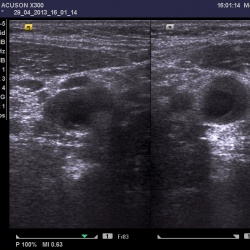

20.05.13. УЗИ мягких тканей. Лимфаденит. Молодая женщина пришла на обследования из-за болезненности в области шеи в подчелюстном треугольнике.Слева в области подчелюстного треугольника...